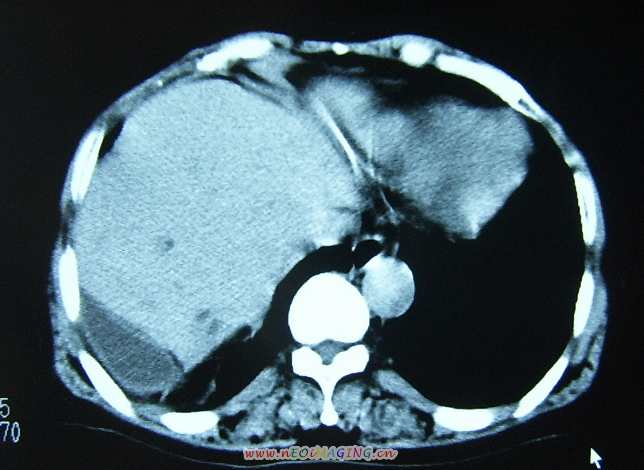

标题: CL0653:【】异位胆囊 [打印本页]

标题: CL0653:【】异位胆囊

女56y右上腹不适数年.

异位胆囊